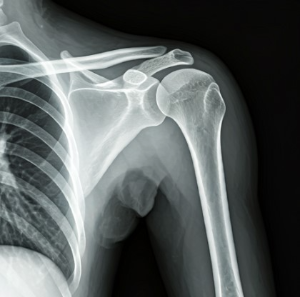

50대는 관절 건강을 관리하는 데 있어 중요한 전환점입니다. 건강보험심사평가원의 통계에 따르면, 무릎관절증으로 병원을 찾는 50대 환자 수가 40대에 비해 무려 3배 이상 증가한다고 합니다. 이는 단순한 숫자가 아닌 우리 몸이 보내는 경고 신호로 이해해야 합니다.

특히 갱년기에 접어드는 여성은 호르몬 변화로 인해 골밀도가 낮아지고 관절의 유연성과 탄력성이 감소하게 됩니다. 이러한 변화는 관절 질환의 위험을 높입니다.

적정 체중을 유지하는 것은 관절에 가해지는 부담을 줄이는 데 필수적입니다. 연구에 따르면 체중이 1kg 감소할 때 무릎 관절에 가해지는 부담이 4kg이나 줄어든다고 합니다.